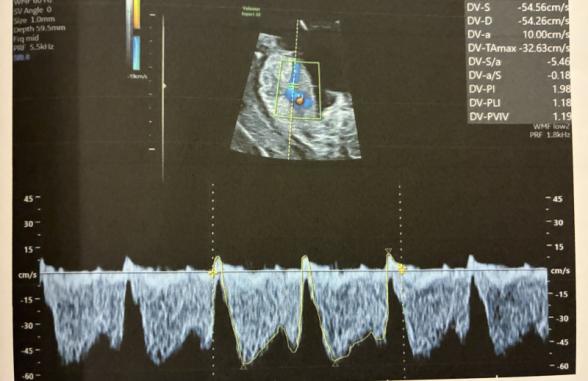

•静脈管(DV)でA波逆転が疑われる(Pl 1.980)